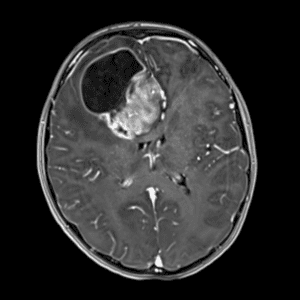

Case #42

Giant cerebral aneurysm